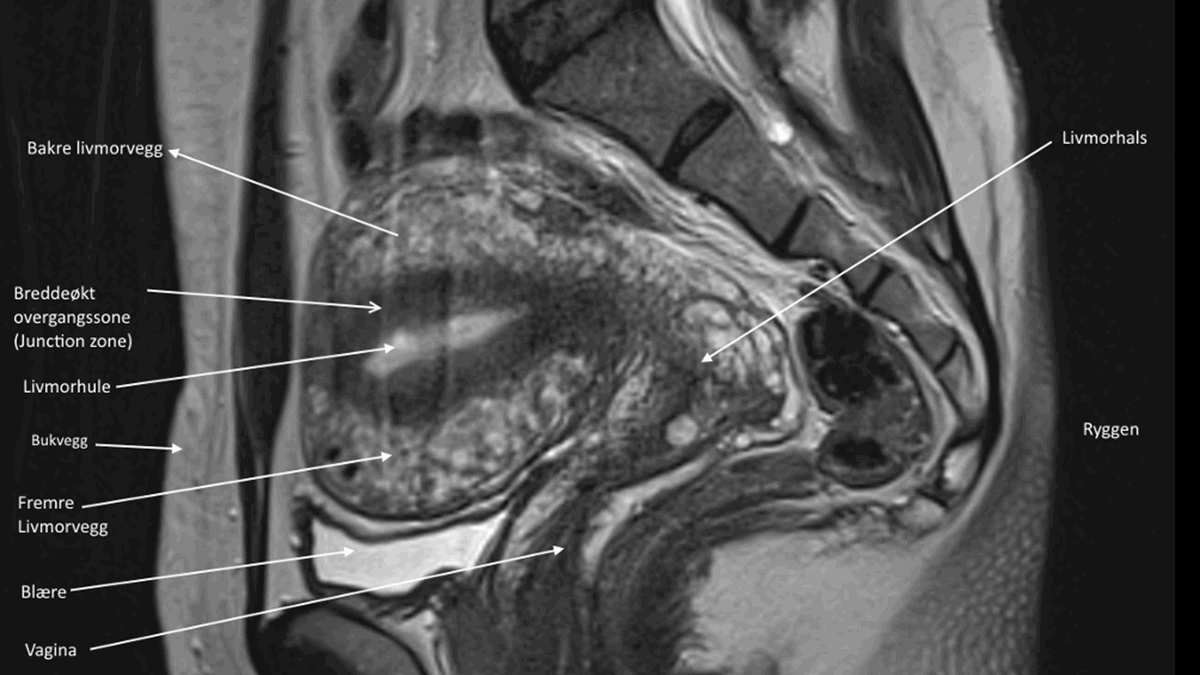

Det er også muligt at stille diagnosen ved en MR-scanning. Med denne metode kan ca. 90% af alle tilfælde blive diagnosticeret korrekt, forudsat at den rigtige undersøgelsesprotokol vælges, og at undersøgelsen bliver gennemført med god kvalitet.

Hvis lægen er usikker på diagnosen efter en indvendig ultralydsundersøgelse, kan der foretages en MR-scanning.